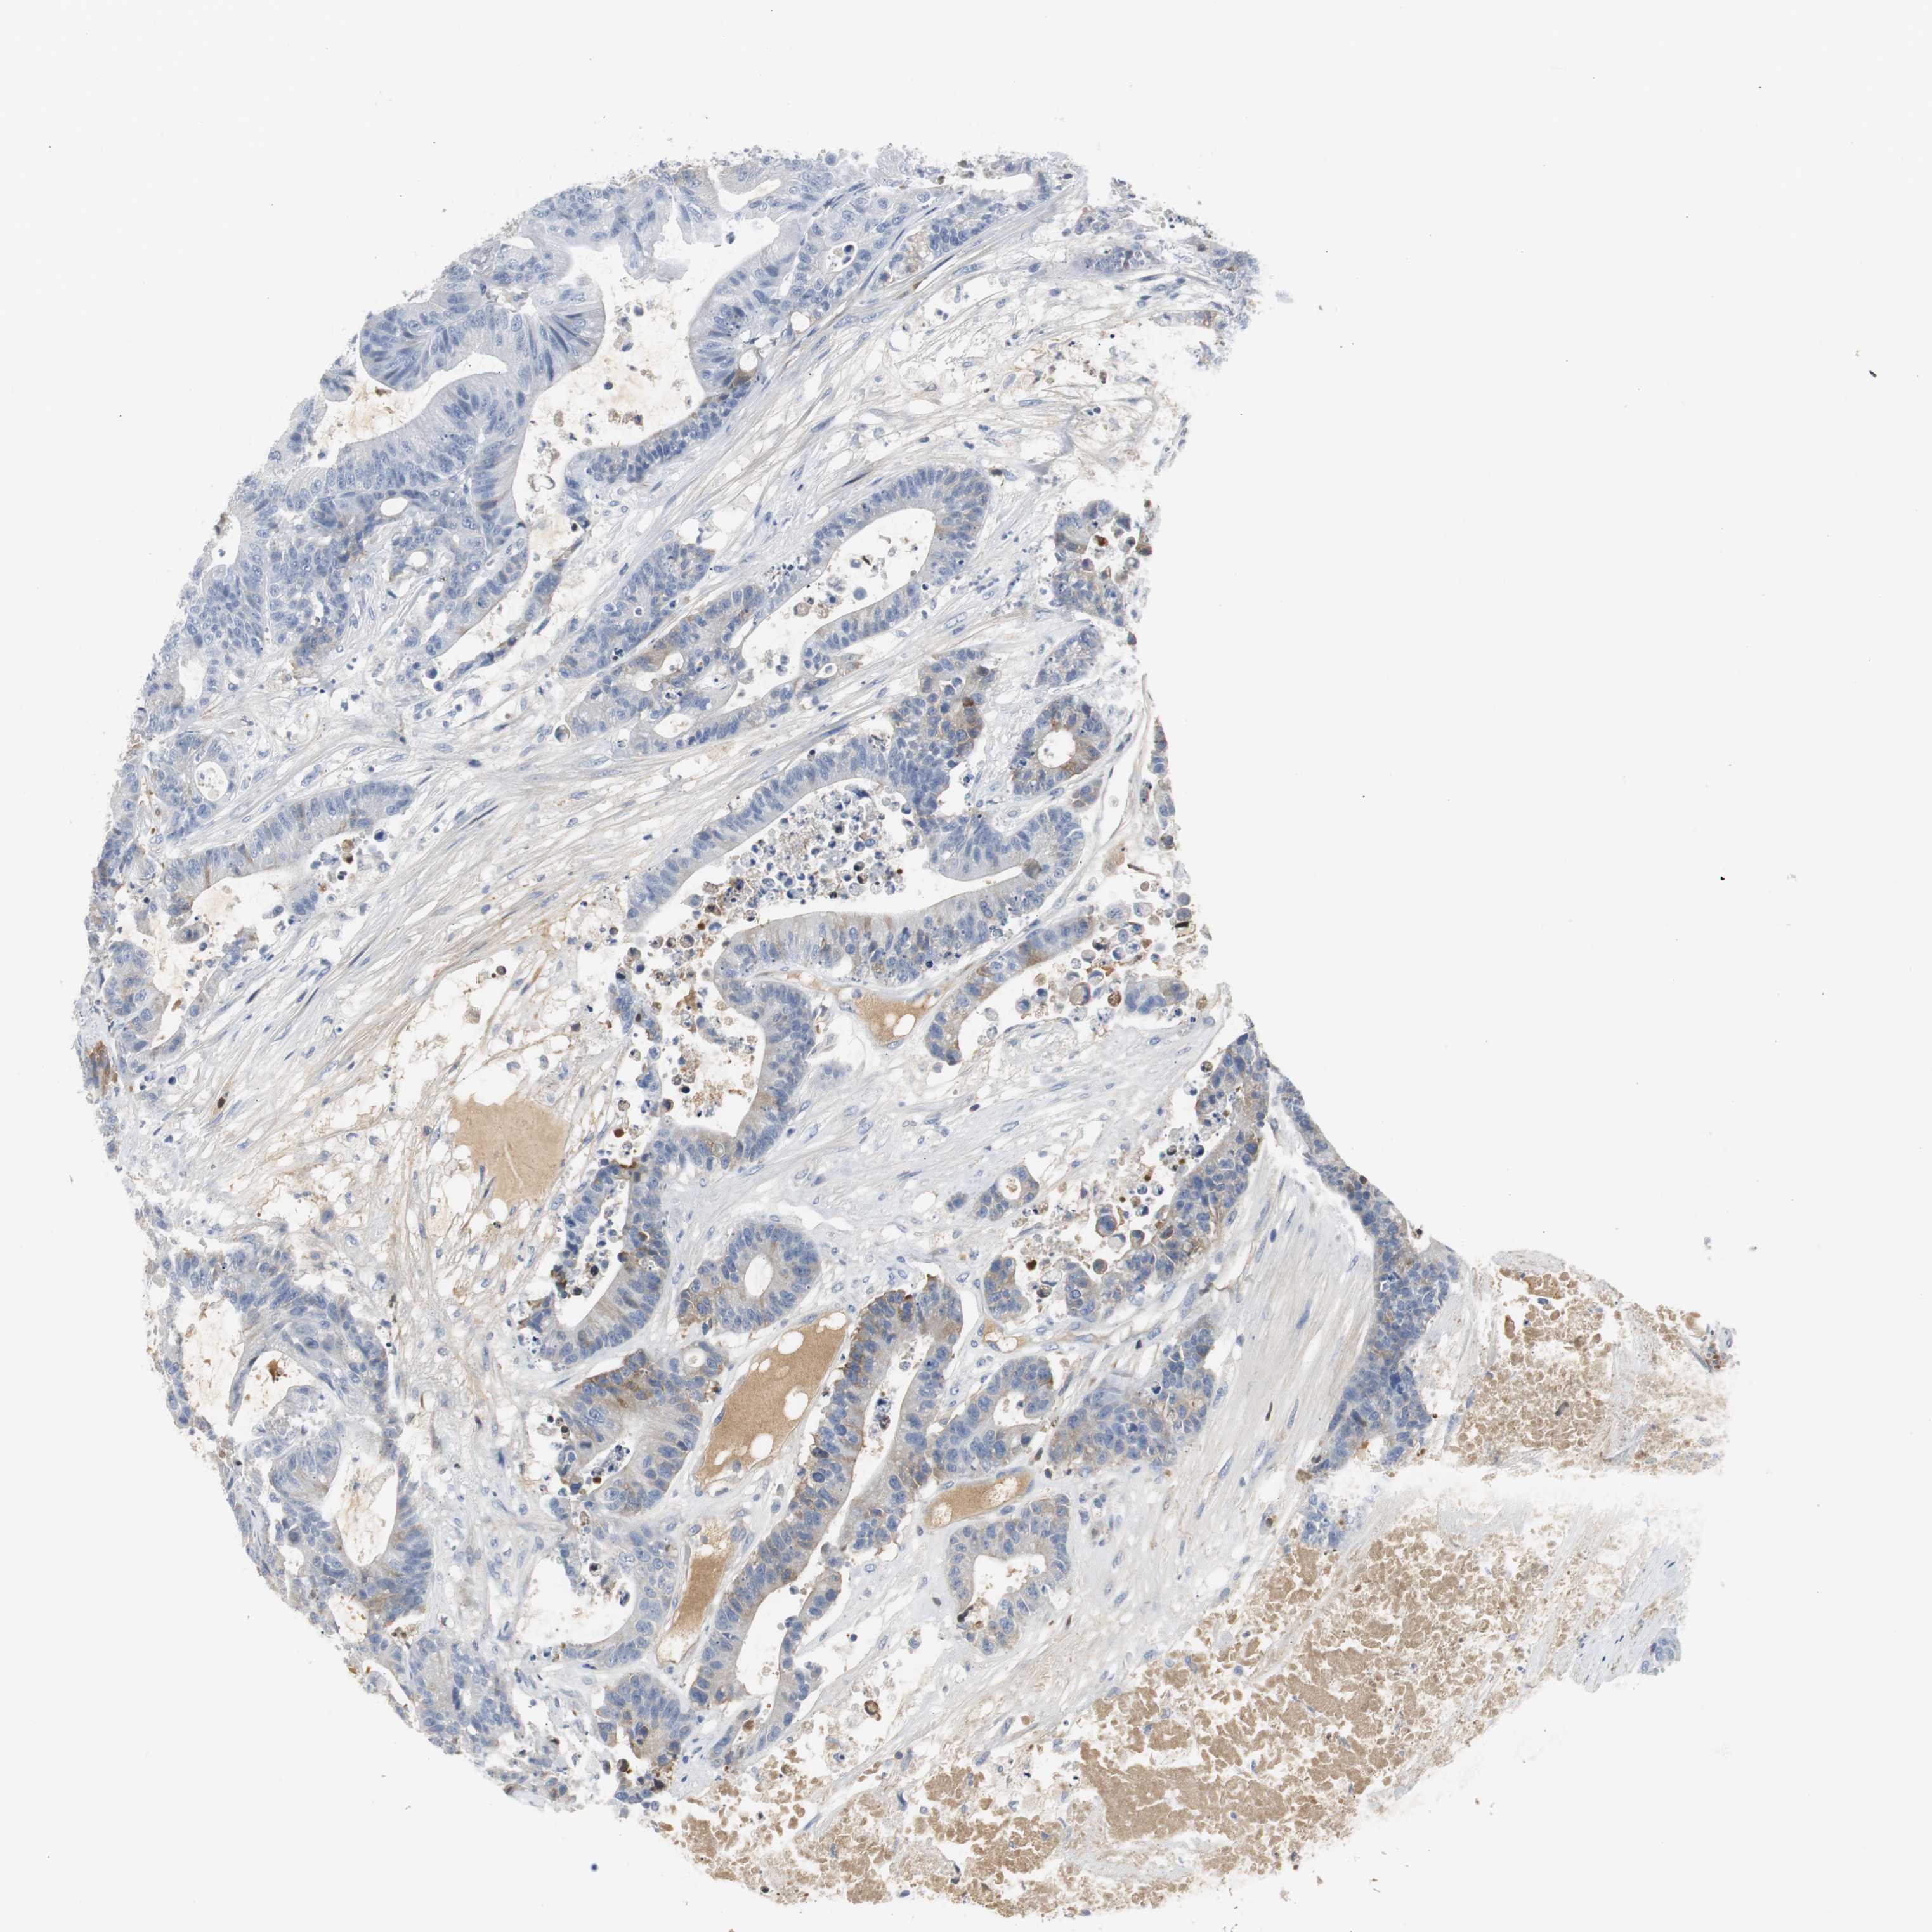

CANCER COLORECTAL CANCER Show tissue menu

Colorectal cancer

Human cancer

Colon adenocarcinoma

Rectum adenocarcinoma